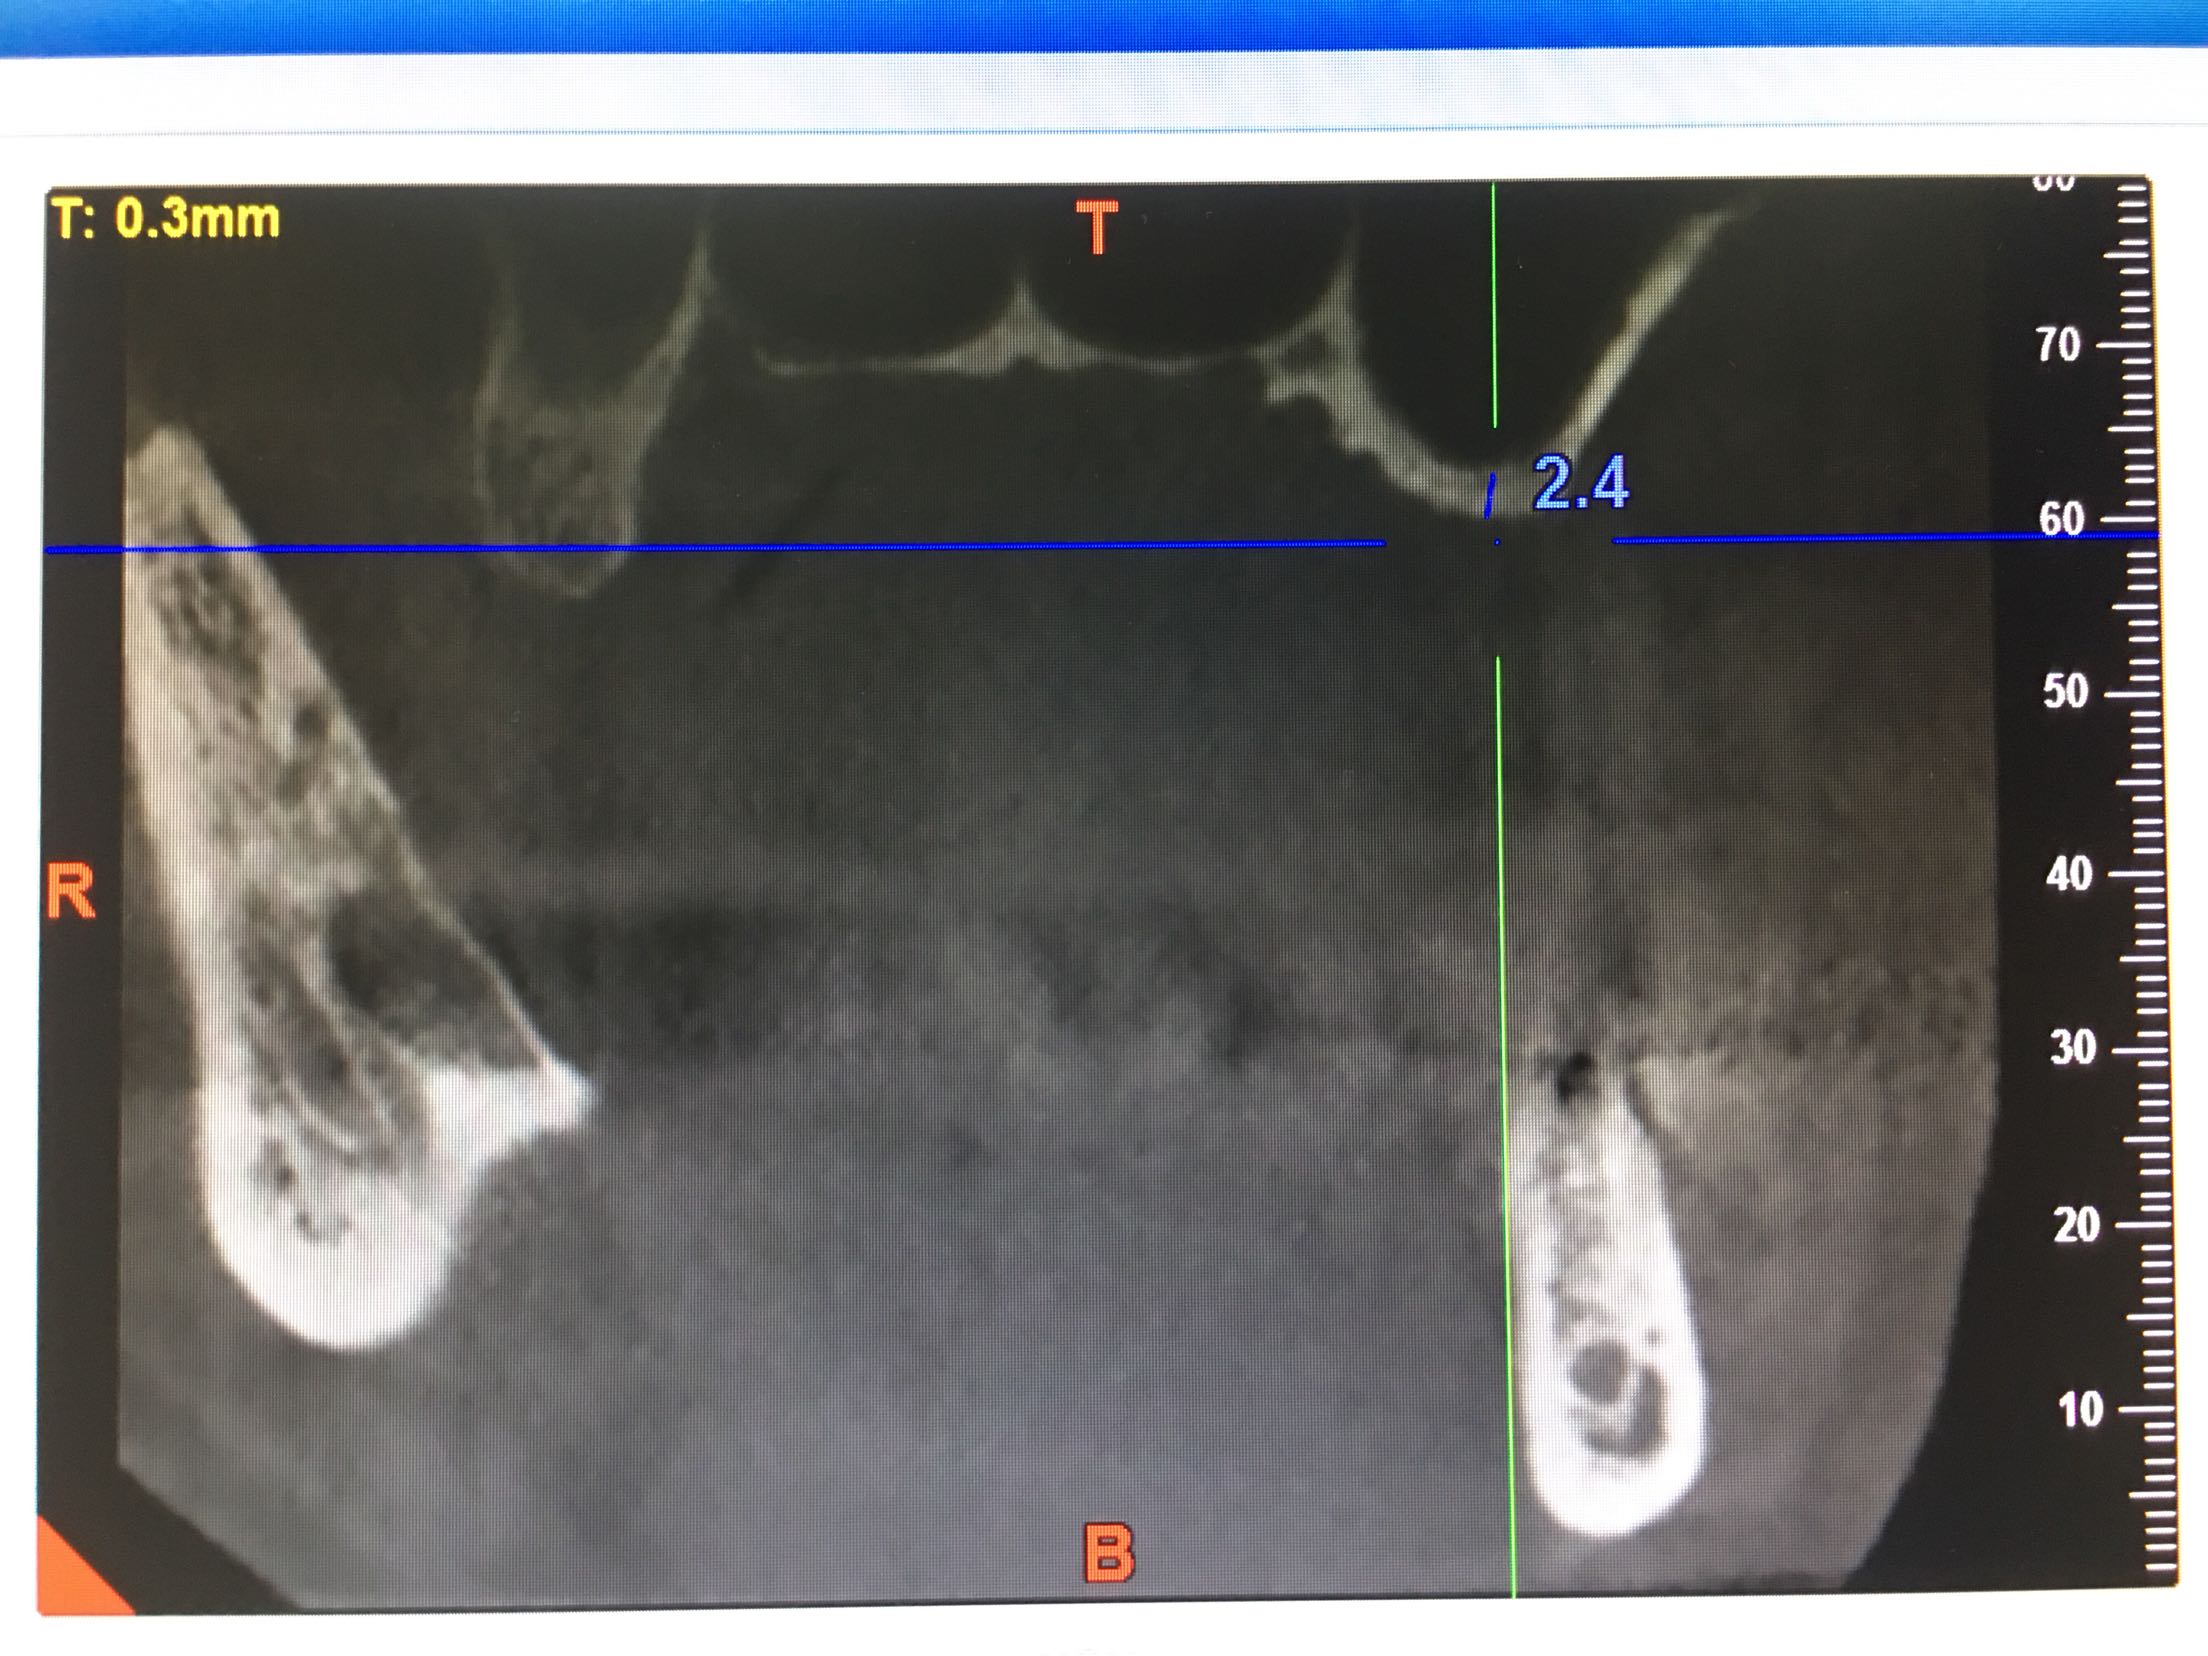

上颌窦底27只有2.4mm,26有4mm

期待半年后的效果,最主要的挑战:每天15支吸烟史,上颌窦黏膜菲薄,27牙上颌窦底只有2.4mm,超出即刻种植5mm的界限!